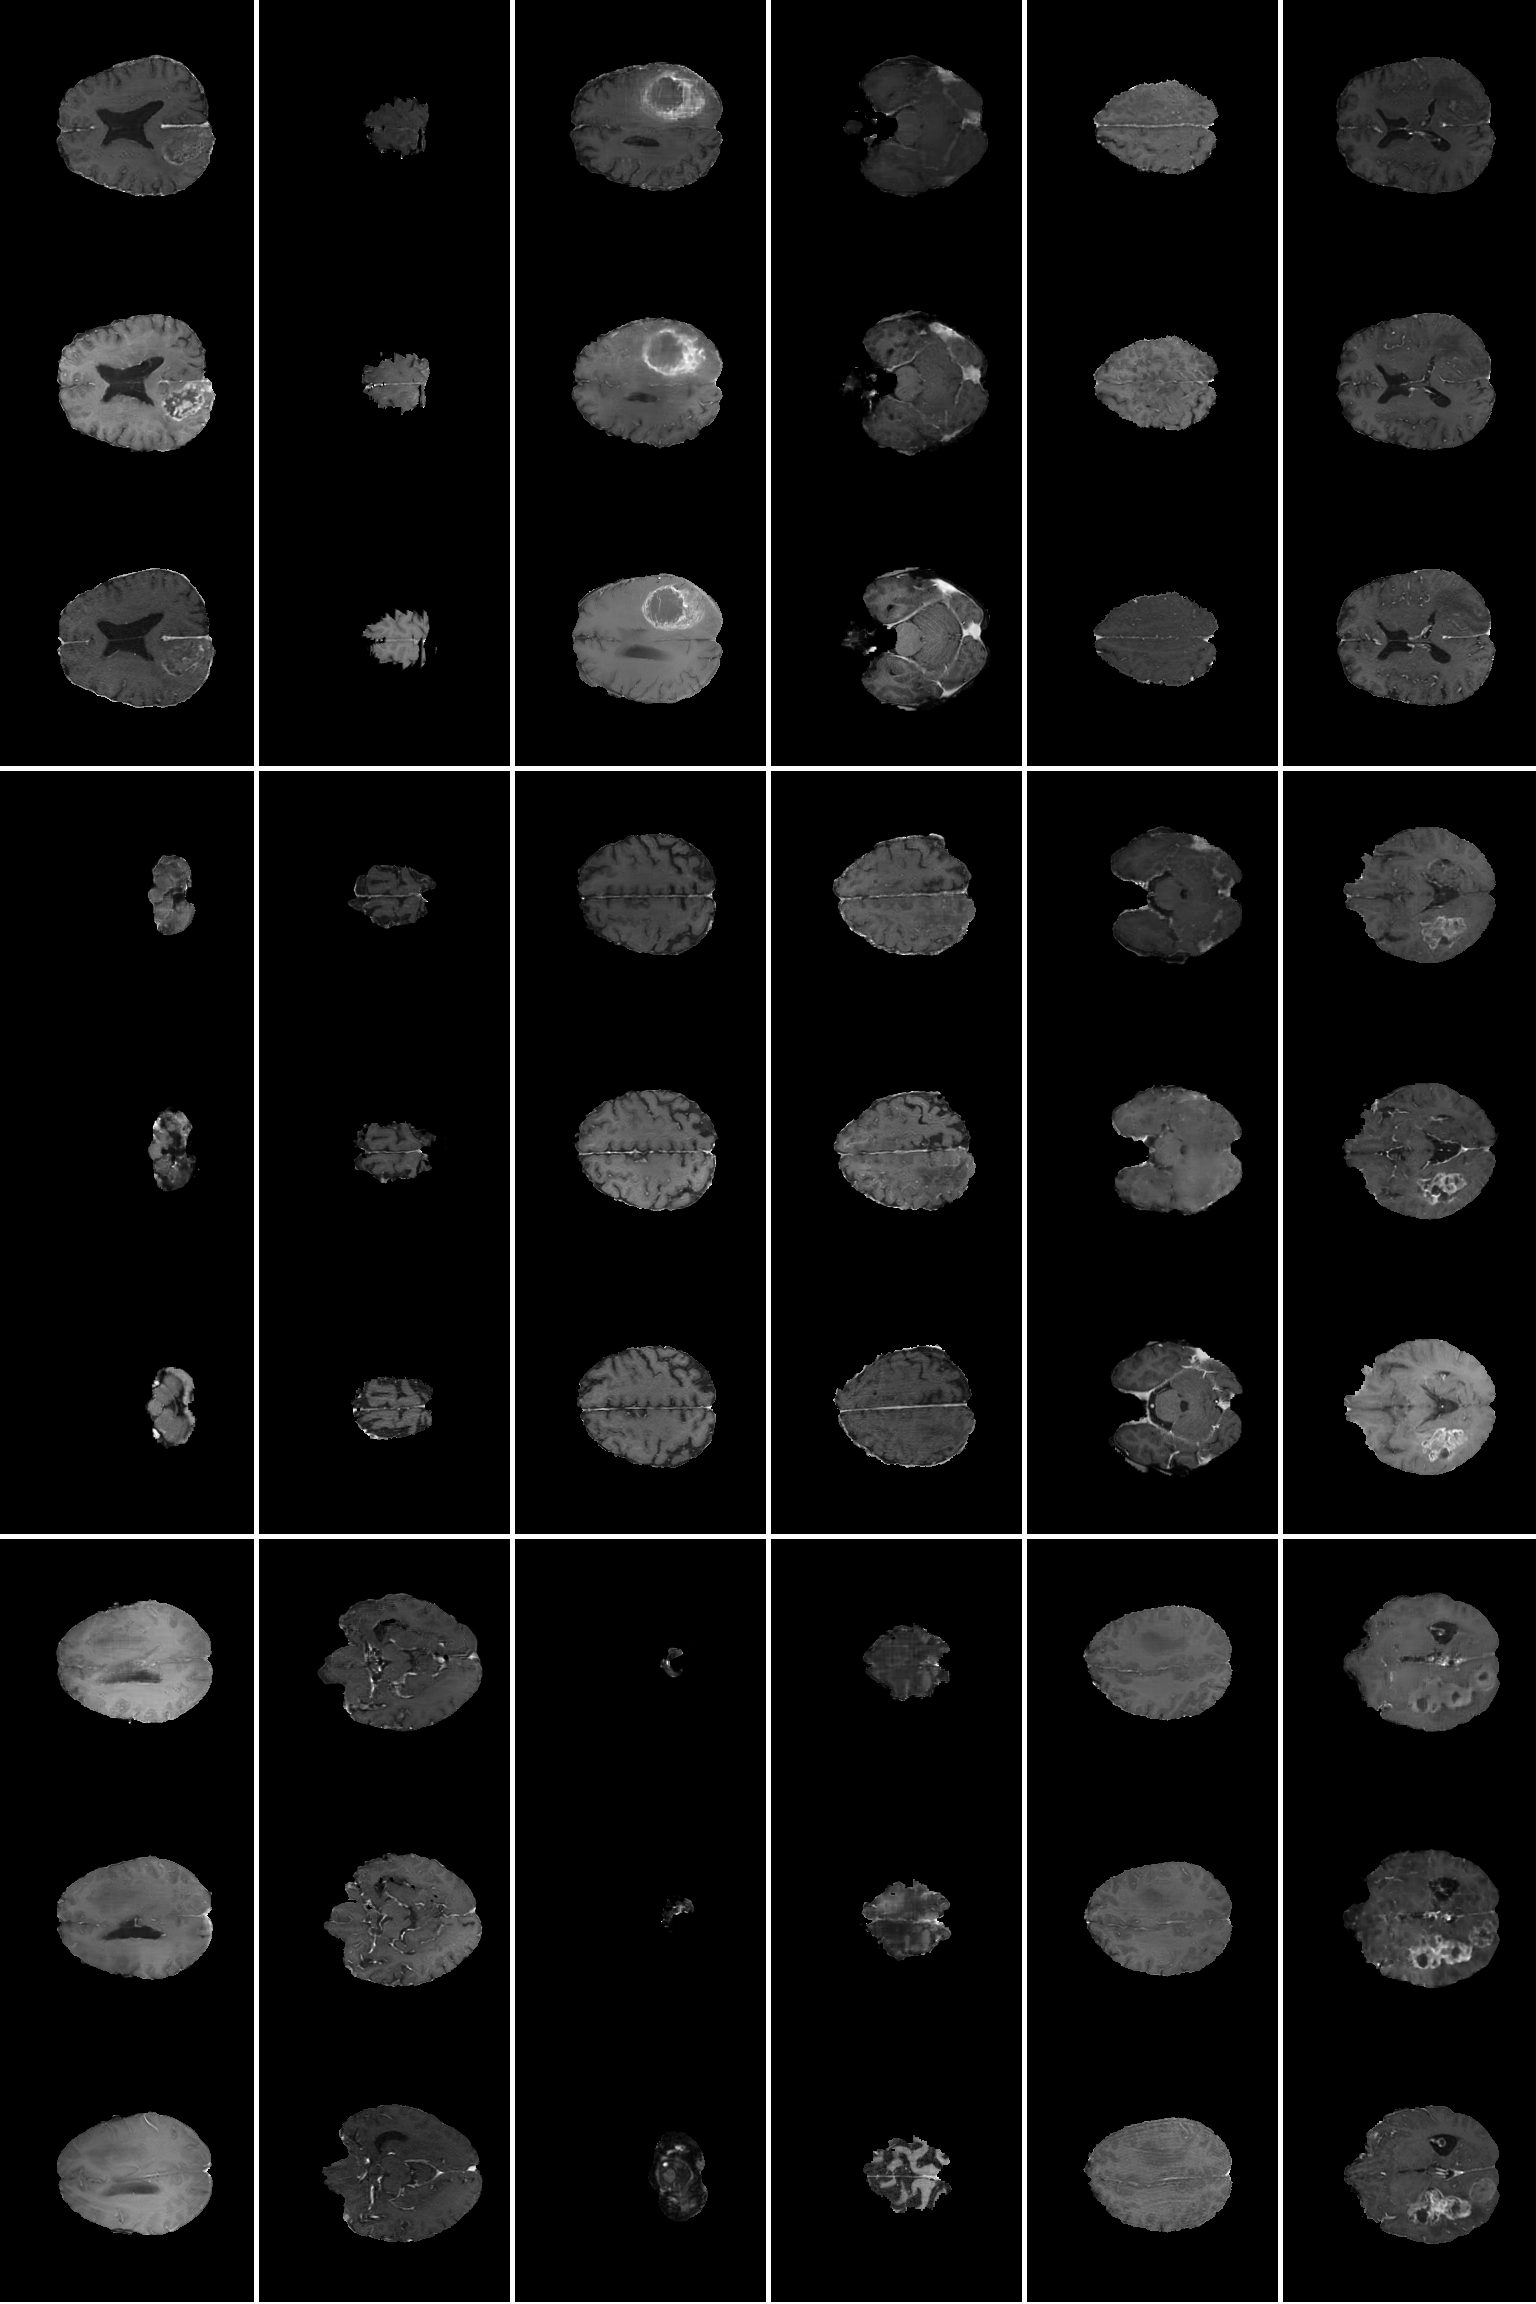

The SPADE instance that was trained on the full BraTS dataset (26,040 image pairs) required 2 days, 13 hours and 26 minutes to complete a total of 50 epochs. The instance that was trained on the reduced dataset (5,208 image pairs) required 3 days, 7 hours and 2 minutes to complete a total of 250 epochs. See figure 5 and 6 for 24 examples respectively of MR images generated with the preprocessed segmentation masks generated via PGAN. Additionally, see figure 7 for examples of MR images generated with the (real) test data from BraTS.

Refer to caption

Fig. 5: 24 examples of pairs of synthetic MR images and corresponding synthetic segmentation masks, generated from the full BraTS dataset. The top image in each rectangle shows an MR image generated by SPADE, and the bottom image shows the corresponding PGAN-generated segmentation mask that was used to generate it.

Fig. 6: 24 examples of pairs of synthetic MR images and corresponding synthetic segmentation masks, generated from the reduced BraTS dataset. The top image in each rectangle shows an MR image generated by SPADE, and the bottom image shows the corresponding PGAN-generated segmentation mask that was used to generate it.

Fig. 7: 18 examples of MR images synthesized from both (full and reduced) training instances, when given (real) segmentation masks from the test set as inputs. The top and middle images in each rectangle shows MR images that have been generated by the full and reduced SPADE instances respectively, and the image below them shows the corresponding true MR image from the test set.